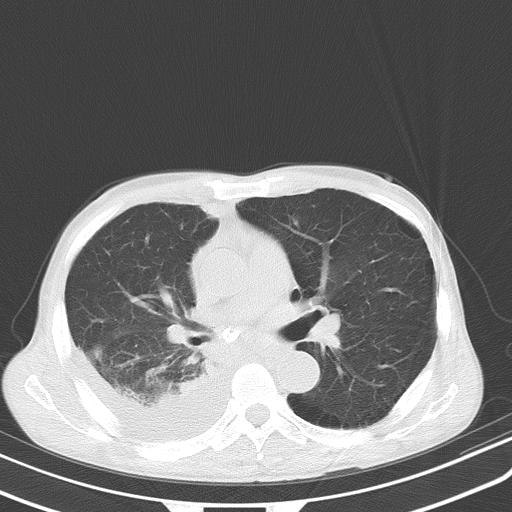

男性 75  咳嗽 一周前发热最高达39

右肺继发型tb并右侧tb性胸腔炎,右侧胸腔大量积液并右下肺膨胀不全,慢支肺气肿、多发肺大泡。建议抽胸水实验室检查并复查排除恶性在占位。

右上肺继发型肺结核,右胸腔中等量积液。

左上肺大泡。

结核的基础上有纵隔淋巴结肿大,右侧有胸水,但右侧纵隔反而窄,说明有肺有不张。

再就是右下肺有块影,和不张混合,还是不能除外肺癌。

补充材料,患者2月份ct片大致正常,双侧胸腔积液,2月份抽胸水未发现ca细胞,现患者发热,痰多,各气管通畅,

1)右肺继发型肺结核。2)左肺胸膜下多发性肺大泡。3)右侧胸腔积液。